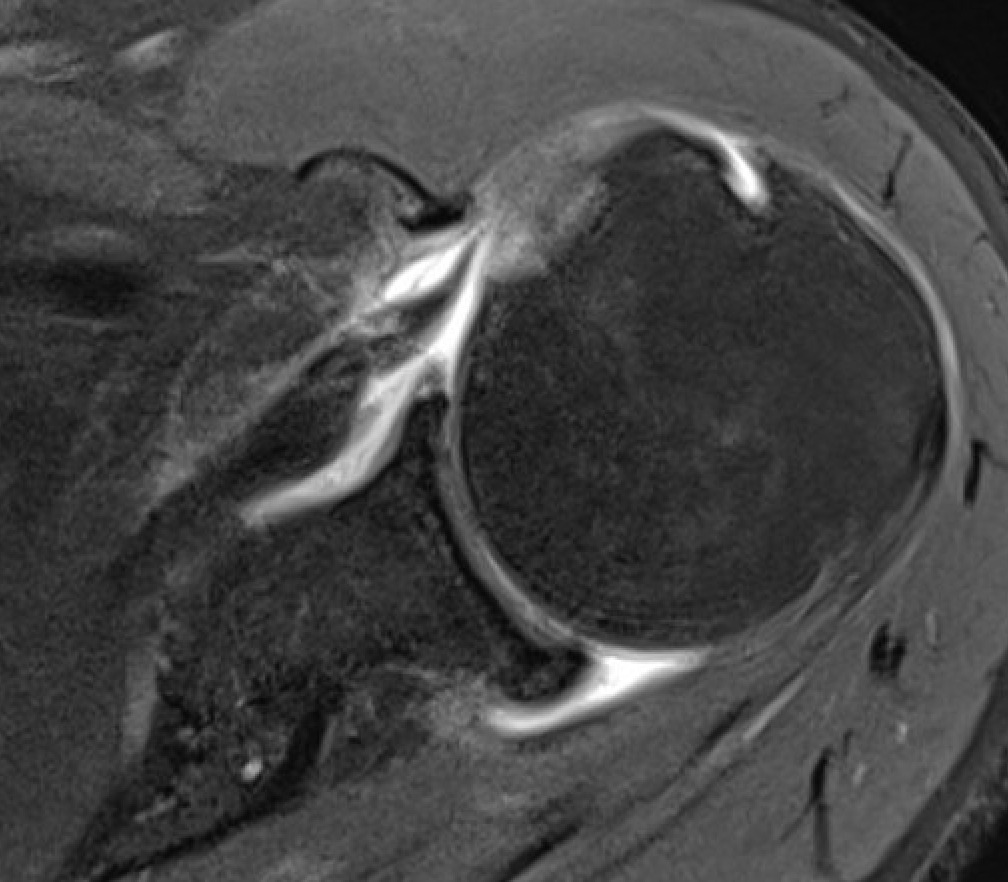

Normal

Medial Subluxation